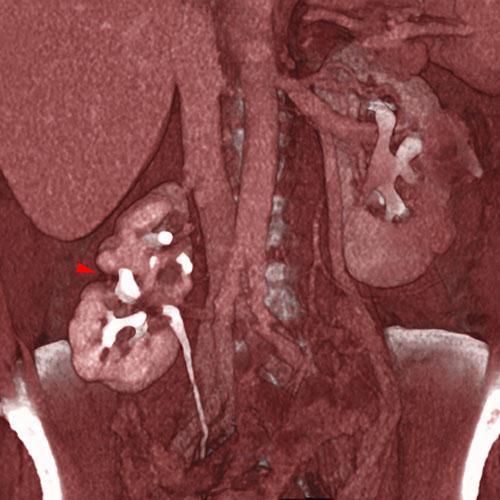

Riñón ectópico pielonefrítico

VR secccional. Visión coronal anterior. TC contrastado en fase excretora. Se aprecia un riñón derecho ectópico, de cortical atrófica, con gran lesión cicatrizal (punta de flecha) coincidente con el caliz dilatado confirmando el diagnóstico de pielonefritis crónica